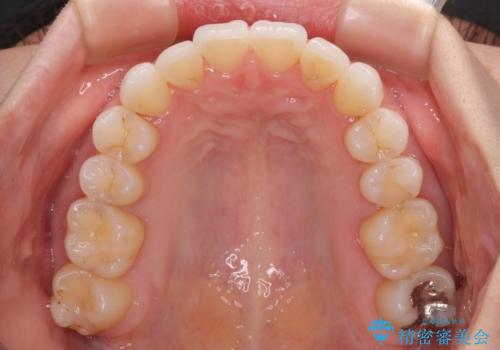

- 上下前歯のデコボコ、特に右上の八重歯を気にして来院された患者様です。

治療後半では悪阻によりマウスピースの装着時間が不十分となることもありましたが、それよりも前にしっかりと装着時間を守って治療を進めることができたため、特に気になるところなく治療を終えることができました。